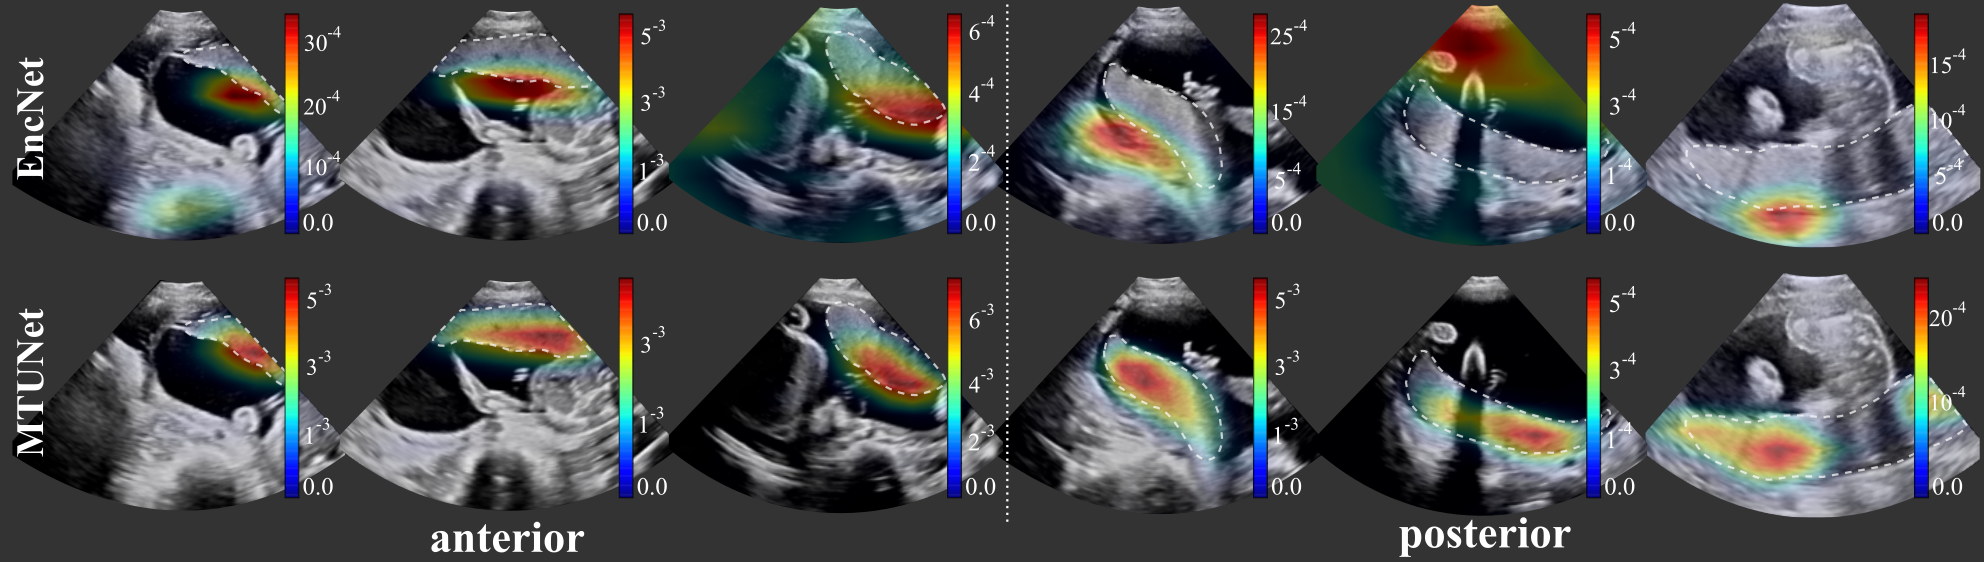

Classification. The classification results (balanced accuracy, precision, F1-score) obtained by all models are reported in Table 1 and examples of attention maps are shown in Fig. 3. The model EncNet trained on the full classification training set of images (depending on the fold), is a strong baseline and achieved high performances on all three measures, and in particular a precision of , and for the classes anterior, none and posterior, respectively.

Although the training set for classification is smaller for the multi-task models, their performance on this task is competitive with the baseline EncNet trained on the full training sets. Both multi-task models outperform the baseline for classes anterior and posterior, suggesting that the additional segmentation task has an influence on the performance on the pretext task. This is also confirmed by the better performance of the models trained on the segmentation set AP. As an example, the model TMTUNet achieved a balanced accuracy of for class anterior when trained on set A, and when trained on set AP. The difference between the models is that the latter uses also manual segmentations of posterior placentas during training, and this increases the performance of the classification of anterior placentas. A final observation is that EncNet performs better for class none (precision and F1-score) than the multi-task models, which can be explained by the larger number of training images, and that this class is not considered in the downstream task.

We show attention maps obtained by models EncNet and MTUNet in Fig. 3. In EncNet, the model’s attention lies rather at the boundary of the placenta and surrounding tissue/space than on the placenta itself. The additional training on segmentation in model MTUNet, yields attention maps with good placenta localization.